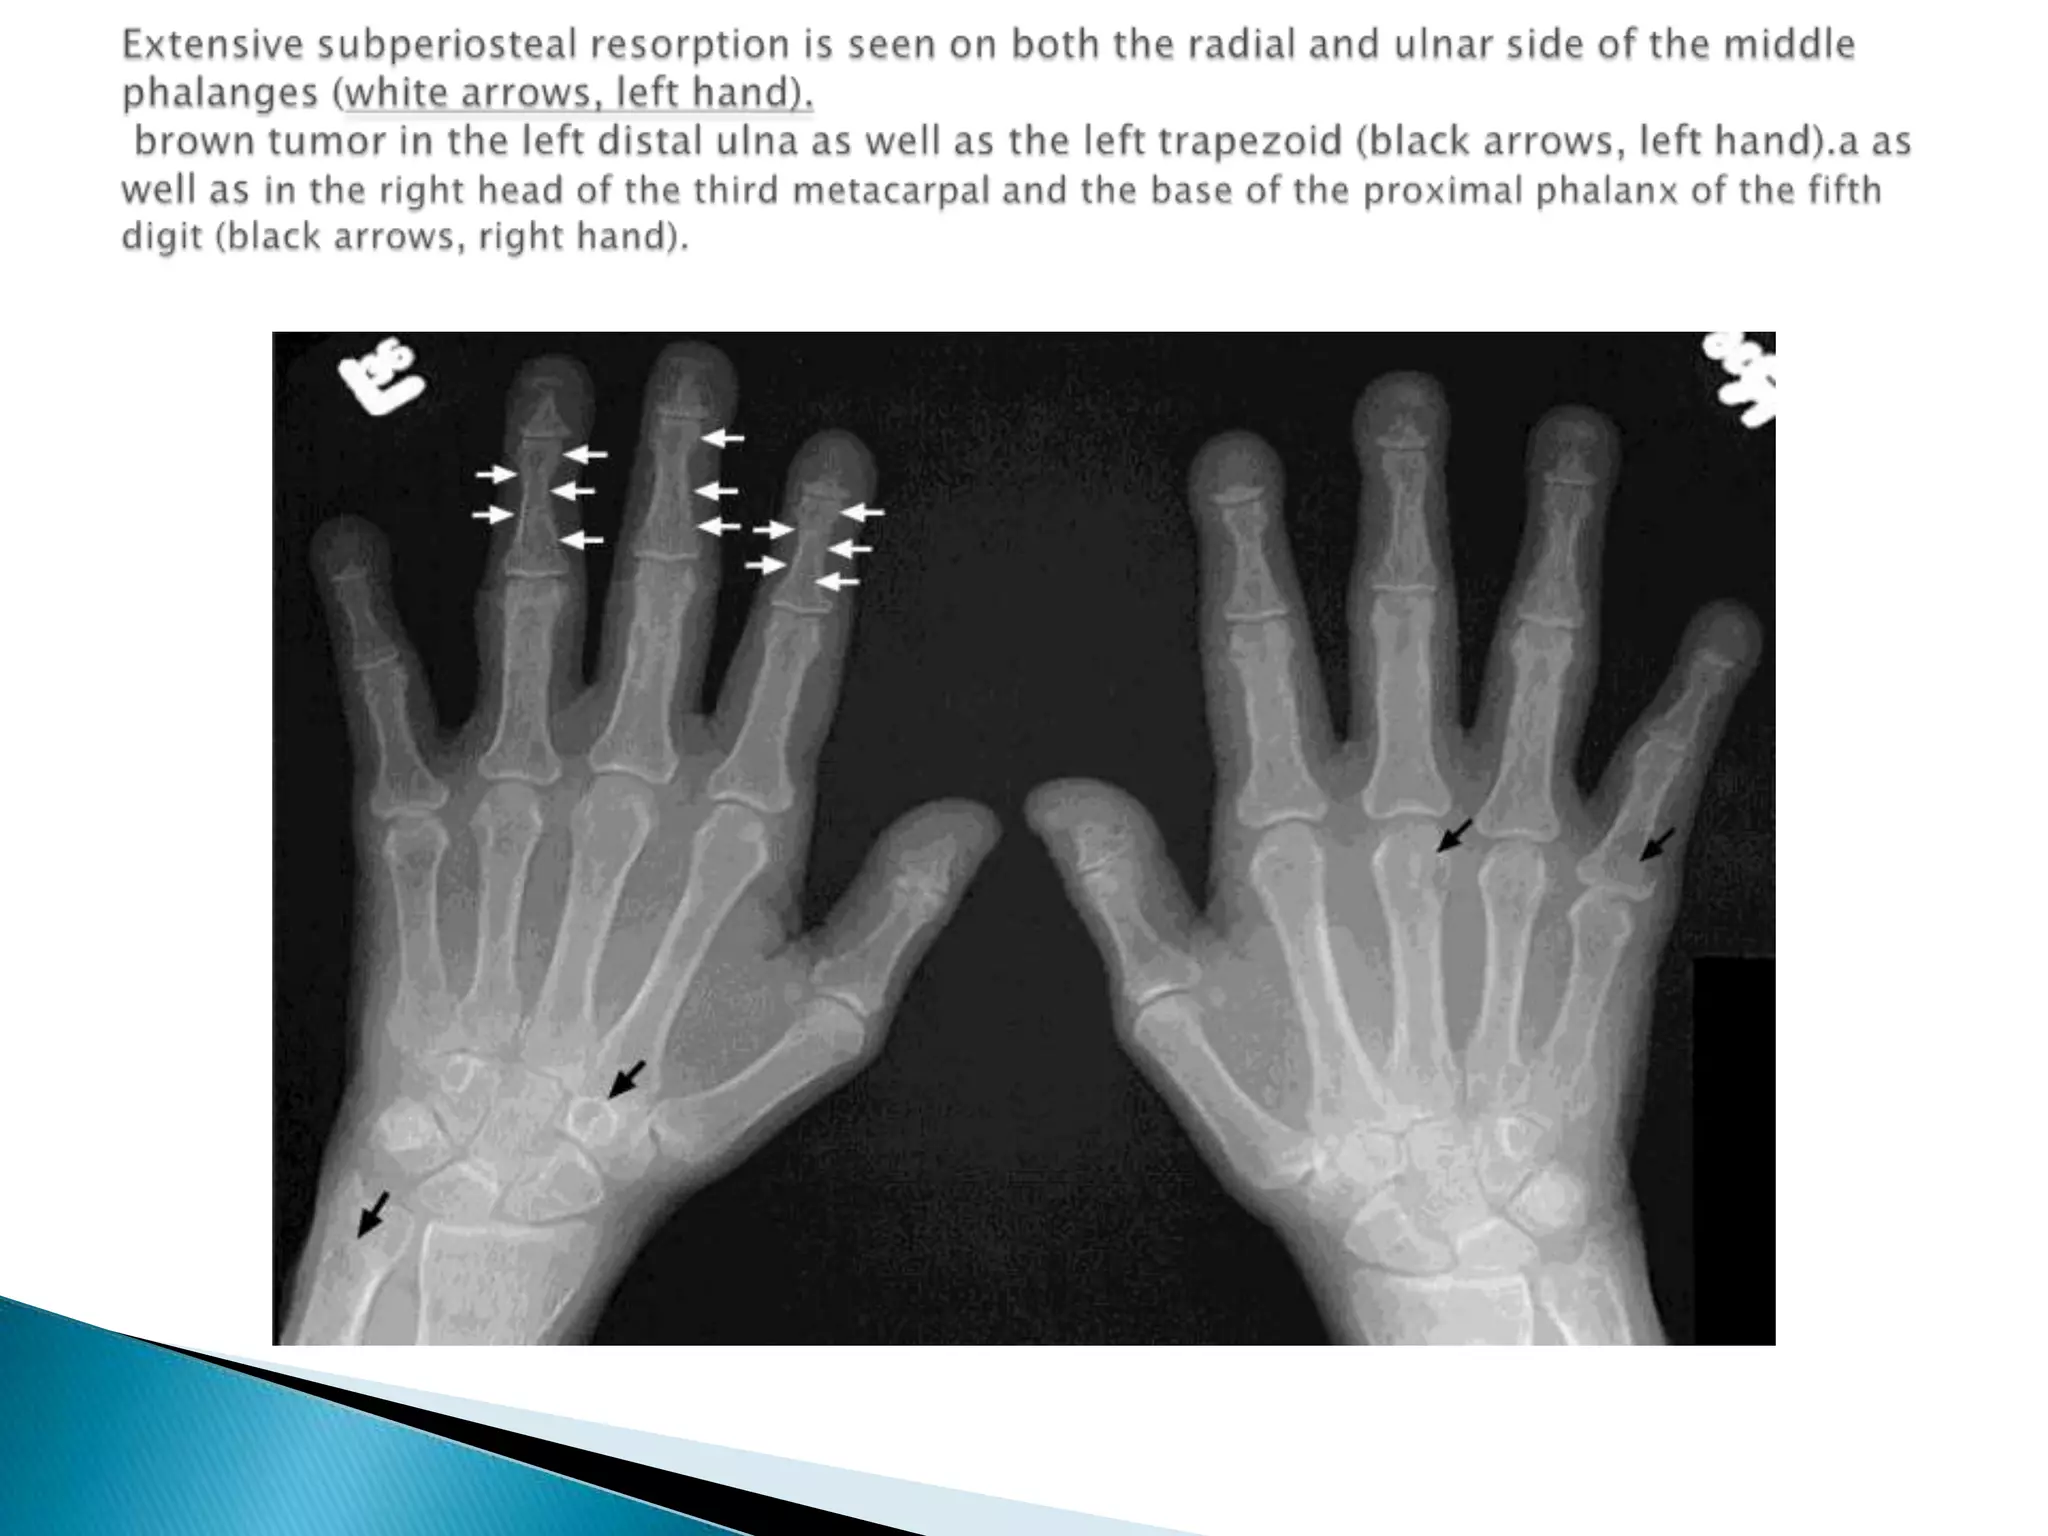

Radiological features of hyperparathyroidismGeneralized decrease in bone density.The hallmark of hyperparathyroidism is subperiosteal bone Resorption.Soft tissue calcification; vascular & chondrocalcification  sometime occur.Brown tumor are occasionally present which are small lytic lesion which could be single or multiple

Extensive subperiostealresorption is seen on both the radial and ulnar side of the middle phalanges (white arrows, left hand). brown tumor in the left distal ulna as well as the left trapezoid (black arrows, left hand).a as well as in the right head of the third metacarpal and the base of the proximal phalanx of the fifth digit (black arrows, right hand).